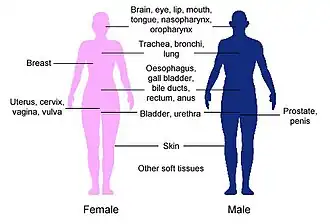

Brachytherapy is commonly used to treat cancers of the cervix, prostate, breast, and skin.[1]

Brachytherapy can also be used in the treatment of tumours of the brain, eye, head and neck region (lip, floor of mouth, tongue, nasopharynx and oropharynx),[10] respiratory tract (trachea and bronchi), digestive tract (oesophagus, gall bladder, bile-ducts, rectum, anus),[11] urinary tract (bladder, urethra, penis), female reproductive tract (uterus, vagina, vulva), and soft tissues.[1]